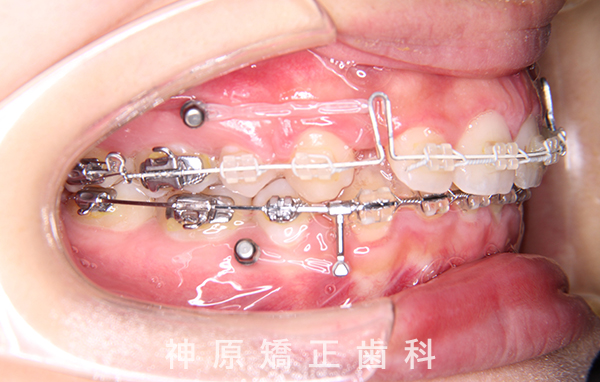

- 治療に用いた主な装置

-

上顎:唇側矯正装置

下顎:唇側矯正装置

歯科矯正用アンカースクリュー - 抜歯 / 非抜歯

- 上下左右第一小臼歯抜歯

口元の突出感を改善するために小臼歯の抜歯が必要と判断しました。抜歯スペースを活用し、前歯を可能な限り後方へ移動させるため、上下に矯正用アンカースクリューを使用する計画です。患者様とご家族に十分な説明を行い、治療ゴールに同意を得た上で矯正治療を開始しました。矯正治療の結果、側貌はE-lineに調和したバランスの良い仕上がりとなりました。